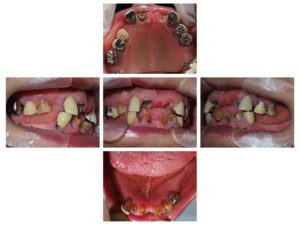

8月21日に全体を治したいとの事で81歳女性が来院されました。

ご本人は歯が折れてどうにもならないと思い、ご相談に来られ、

インプラントも可能だと思いましたが、ご高齢のためインプラントは希望されず、

早く咬合状態を改善するため、ブリッジの方法で

治療を行いました。

8月31日に上下右の1番のコア(土台)をSET、右上2番と6番を抜歯、

右上5番~左上4番の型取りを行いました。

9月13日に正中がズレていたため修正、

下の5番~5番の型取りを行いました。

9月20日に右上5番~左上4番のジルコニア、

下が5番~5番のハイブリッドセラミックをSETしました。

延長ダミーの部分に関しては咬合したとき

負荷がかからない様にしております。